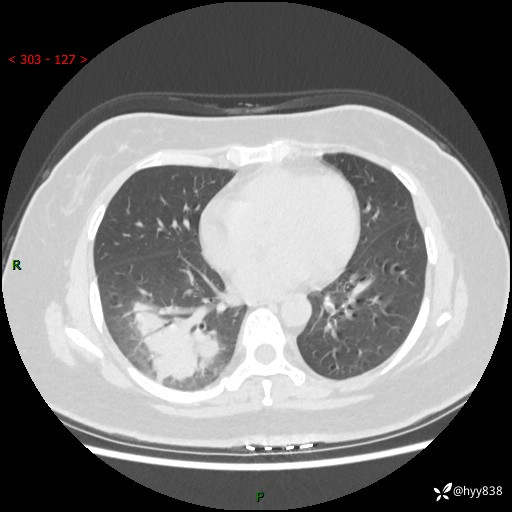

大叶性肺炎的表现形式,晒晒鉴别诊断吧…结果公布~

简要病史:患者8天前无明显诱因出现咳嗽、咳痰,为绿色脓痰,无明显加重与缓解因素,无高热、寒战,无呼吸困难,无大量脓痰,无哮鸣音,于当地医院行胸片示右下肺团块影,性质待定,予口服药物治疗症状未见明显改善,具体药名不详,为求进一步诊治来我院就诊,门诊以“肺占位性病变”收入我科进一步诊治。 患者自发病以来,精神、饮食尚可,睡眠欠佳,大小便正常,体力、体重未见明显异常。

辅助检查:CT

增强动脉期+静脉期